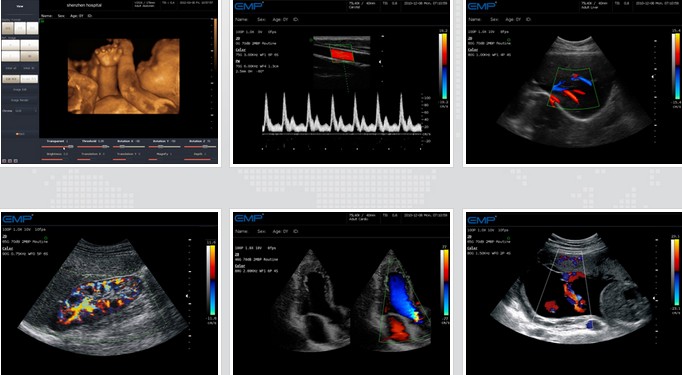

EMP-3000专家版是深圳恩普公司*新推出的一款全身应用型全数字彩色多普勒超声诊断系统,并内置多种图像处理技术,有着很高的通道数

和处理能力,动态范围广,是高性价比机型的理想选择。

应用全数字技术实现高品质图像,适用于腹部、妇科、产科、心脏、泌尿、儿科、血管、介入治疗等领域,满足多种临床诊断要求。

EMP-3000专家版

专家版全数字彩色多普勒超声诊断仪

● 3D/4D成像

● 一键优化技术

● 频率复合成像技术

● 具有方向能量多普勒

● 空间复合成像技术

● B/CFM/PW实时三同步

● 宽景成像技术

● 噪声抑制技术

临床图片